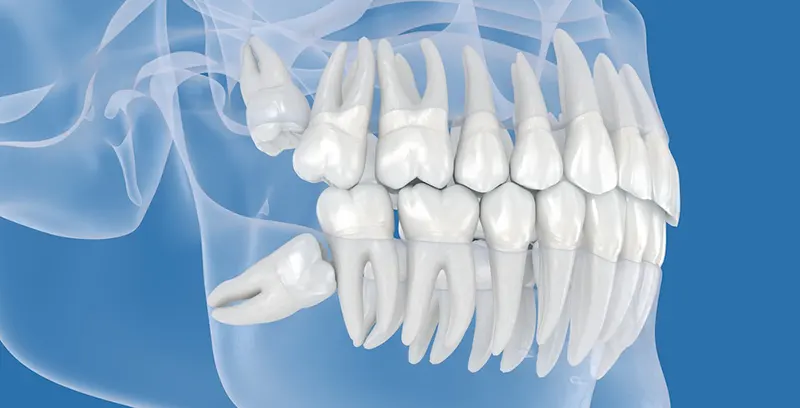

Wisdom teeth are the third and final set of molars that typically emerge during the late teens or early twenties. While some individuals have enough space in the jaw for these teeth to grow in properly, many do not, leading to complications. When a wisdom tooth becomes impacted, it grows at an angle rather than straight through the gum line, which can cause pain, uneven eruption, or partial emergence.

Impacted wisdom teeth can also damage surrounding teeth and jaw structures. Their position makes them difficult to clean, allowing bacteria to accumulate and increasing the risk of infection and decay. For these reasons, removal is often recommended to prevent more serious complications. Routine X-rays during dental exams can help determine whether extraction is necessary.